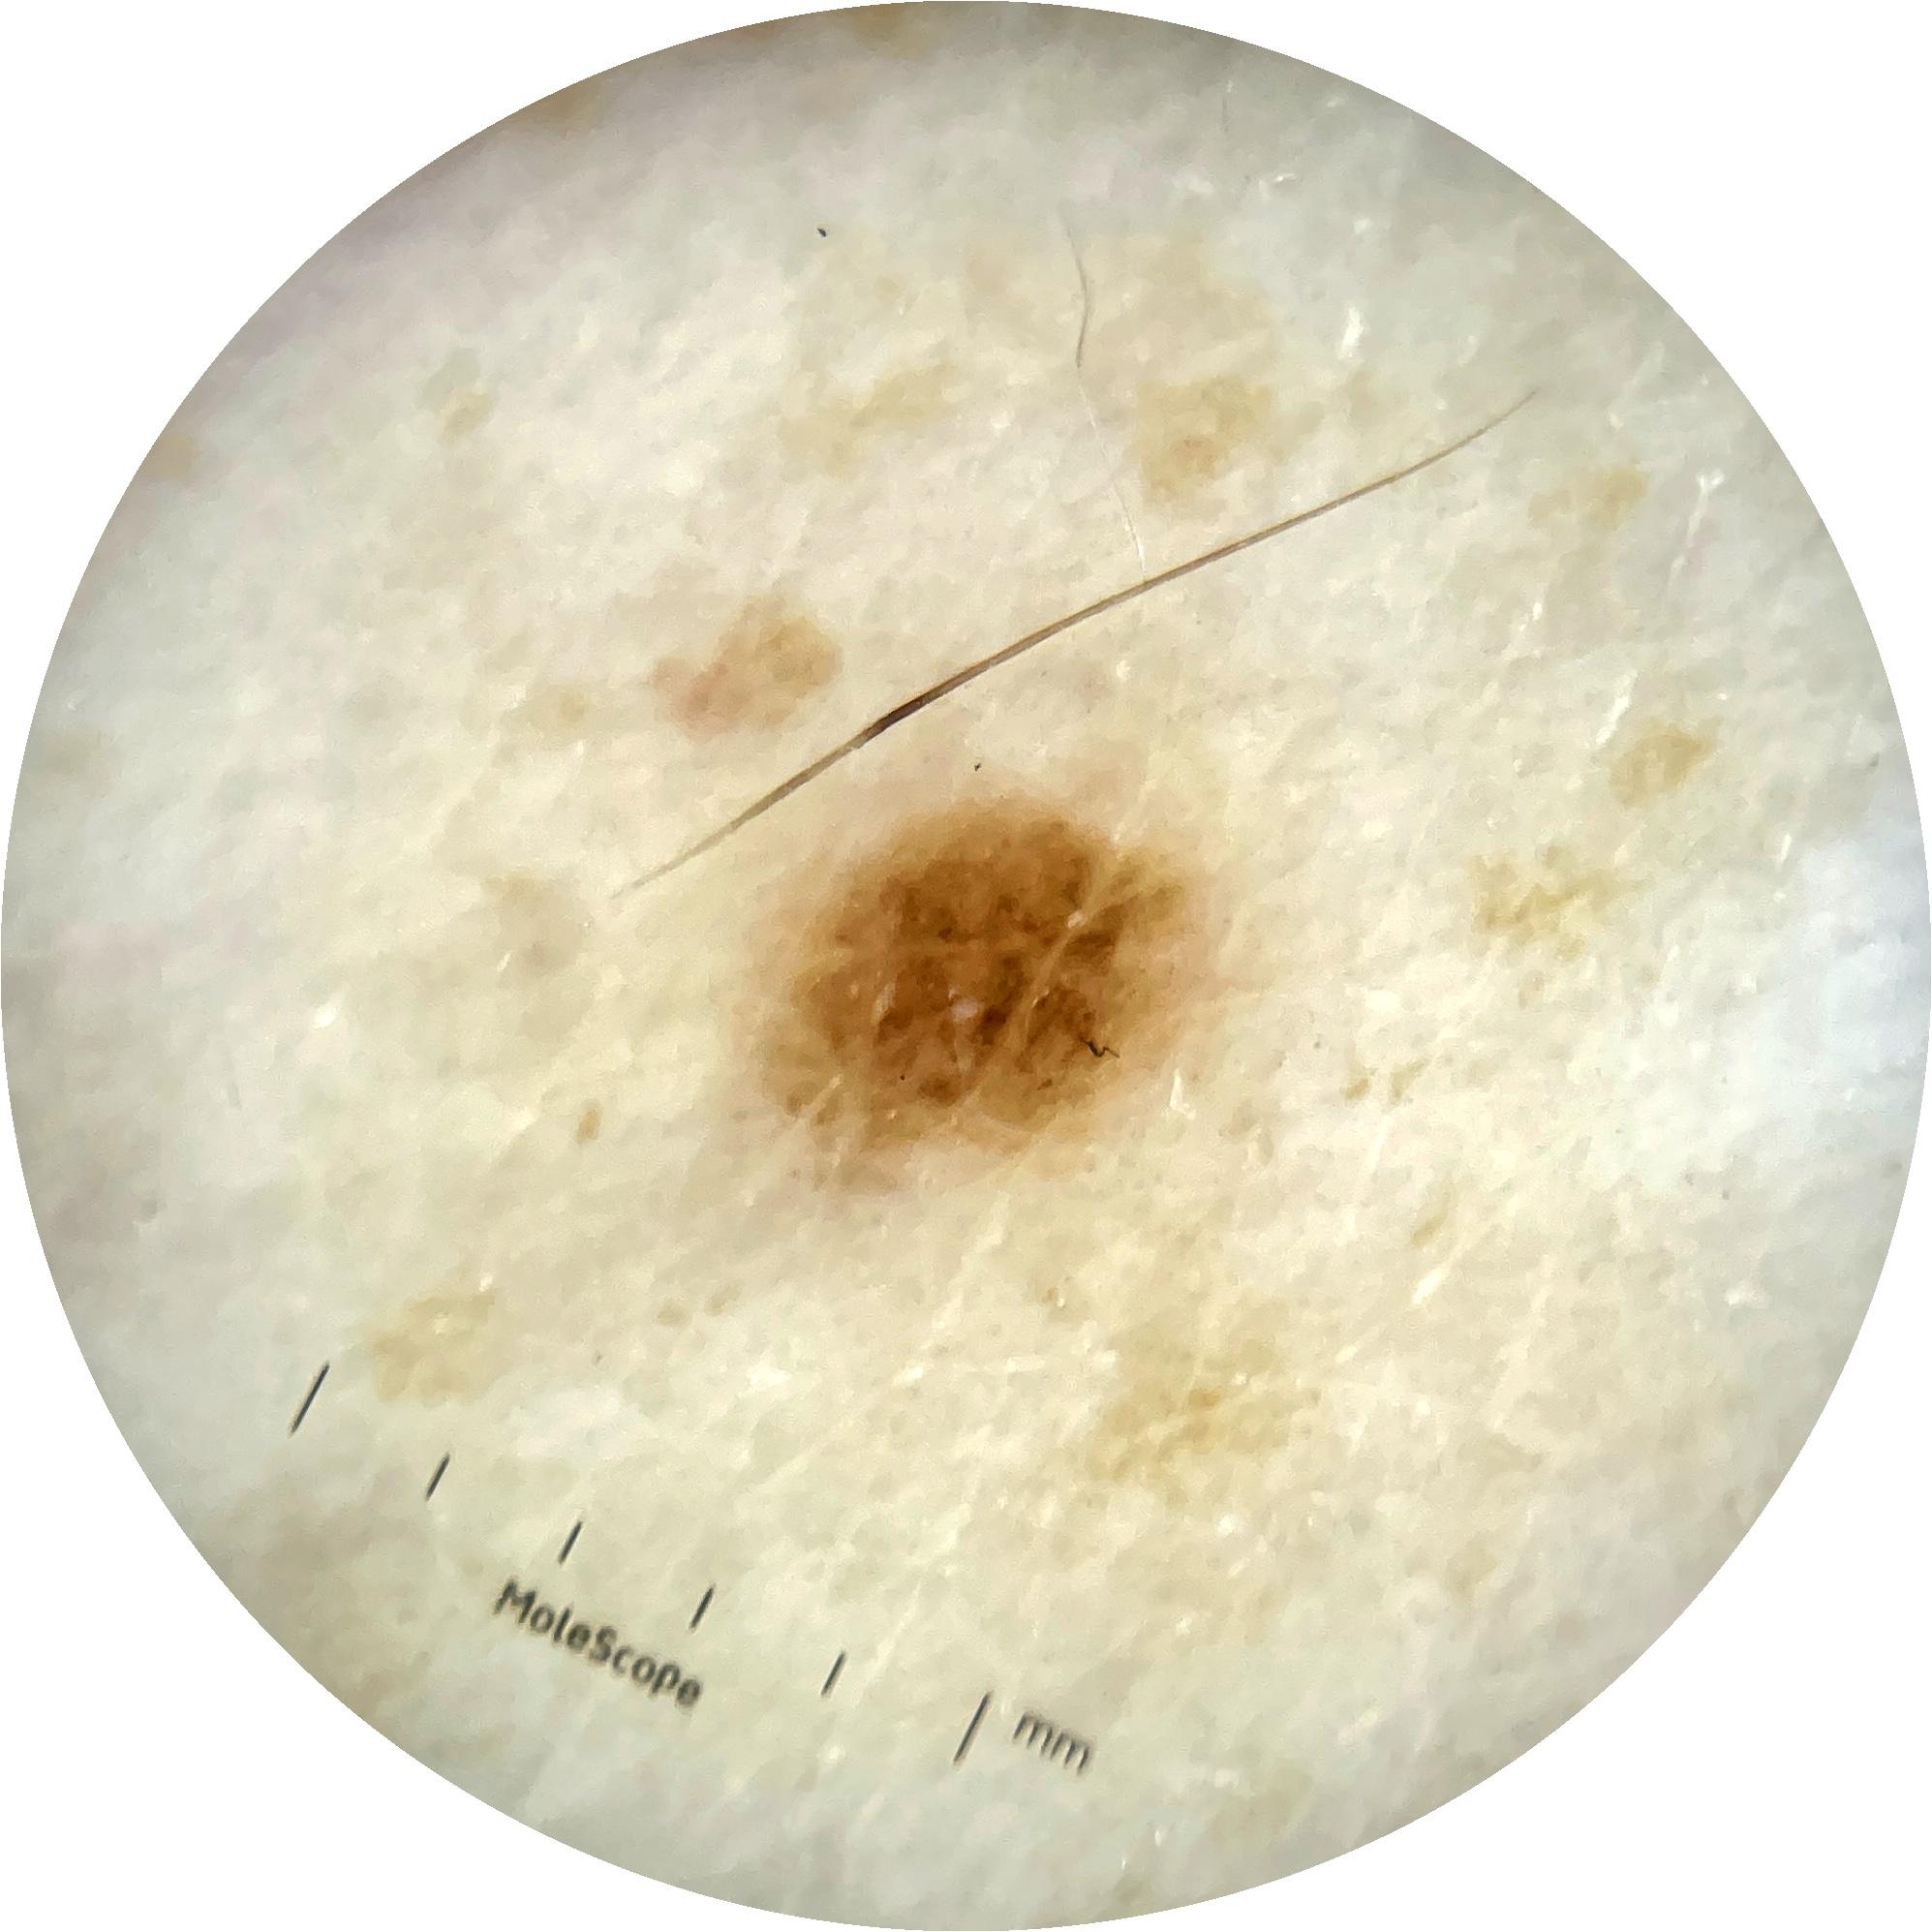

ISIC_9785574

2003 x 2003

Field Value

acquisition_day 148

age_approx 45

anatom_site_1 Head and neck

anatom_site_general head/neck

concomitant_biopsy False

diagnosis_1 Benign

diagnosis_confirm_type single image expert consensus

family_hx_mm True

image_manipulation instrument only

image_type dermoscopic

lesion_id IL_0236417

patient_id IP_8456088

personal_hx_mm True

sex female